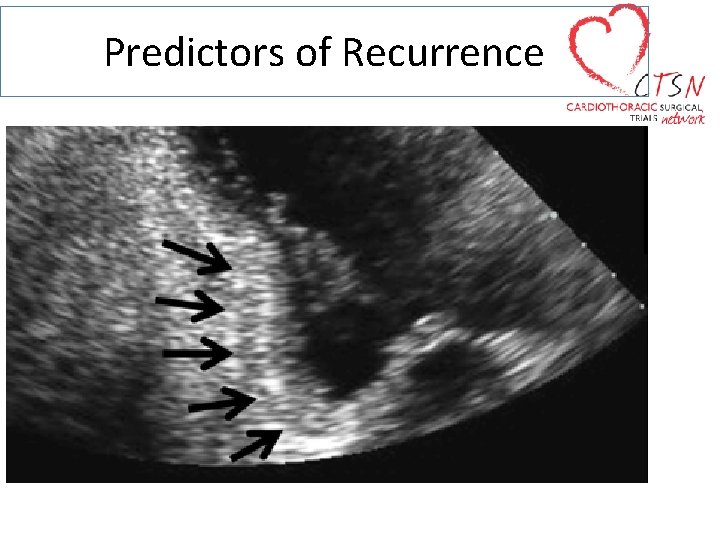

Predictors of Recurrence

Predictors of Recurrence Tenting Area Tenting Height Anterior and Posterior Leaflet Angles

Predictors of Recurrent MR After MVA No or Mild annular dilatation Coaptation depth >1 cm Posterior leaflet angle >45° Distal anterior leaflet angle >25° Advanced LV remodelling LVEDD > 65 mm Systolic sphericity index > 0. 7 End systolic interpapillary muscle distance >20 mm LVESV ≥ 145 ml (or ≥ 100 ml/m 2)